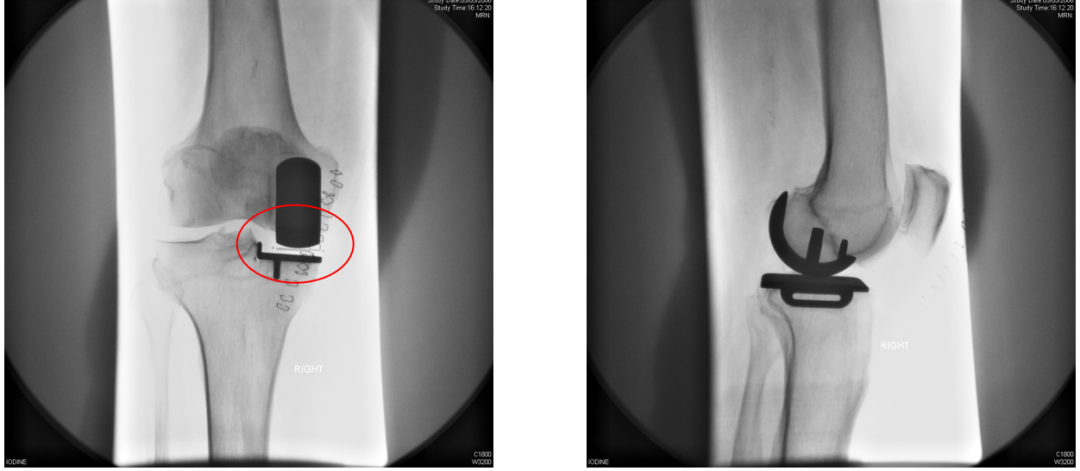

胫骨假体中立位(横断面:无内外旋)

胫骨假体内旋

胫骨假体外旋